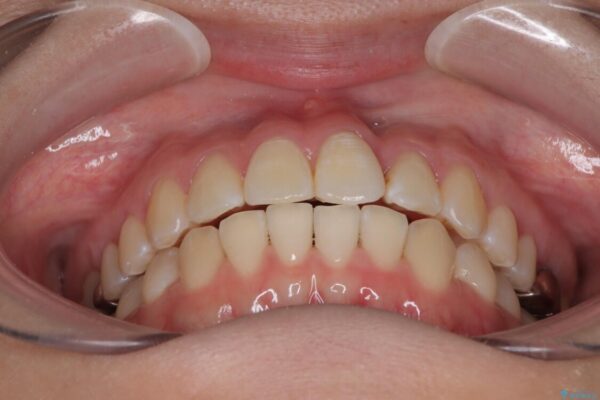

「前歯のねじれを改善したい」とのご希望で当院に来院された患者様です。

診察の結果、上下の前歯部に**叢生(そうせい/歯のガタガタ・重なり)**が認められました。

特に上の前歯にはねじれや重なりがあり、審美的にも清掃性にも影響している状態でした。

治療前

• 前歯のねじれ・ガタガタを10か月で改善!20代女性の矯正治療|クリアブラケットでむし歯になりにくい歯並びへ改善 治療前画像